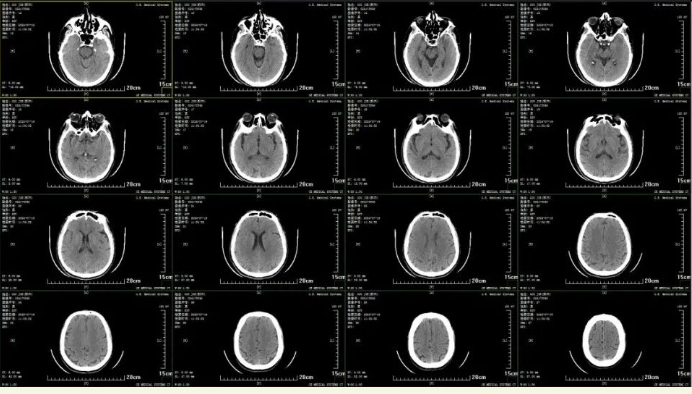

53岁的郭先生在工地上高温作业时,突发意识障碍,约2小时后被紧急送达市一院。入院时,郭先生情况危急,神志不清且无法言语,体格检查无法配合。经神经内科急诊专科医师初步判断是“脑卒中”,快速开启绿色通道完善头部 CT检查。CT显示未见脑出血及坏死低密度区。考虑颅内大血管闭塞,如果不及时进行介入手术治疗,尽快恢复颅内血流灌注,患者将会有生命危险!

术前患者头部CT:颅内少许腔隙性脑梗塞